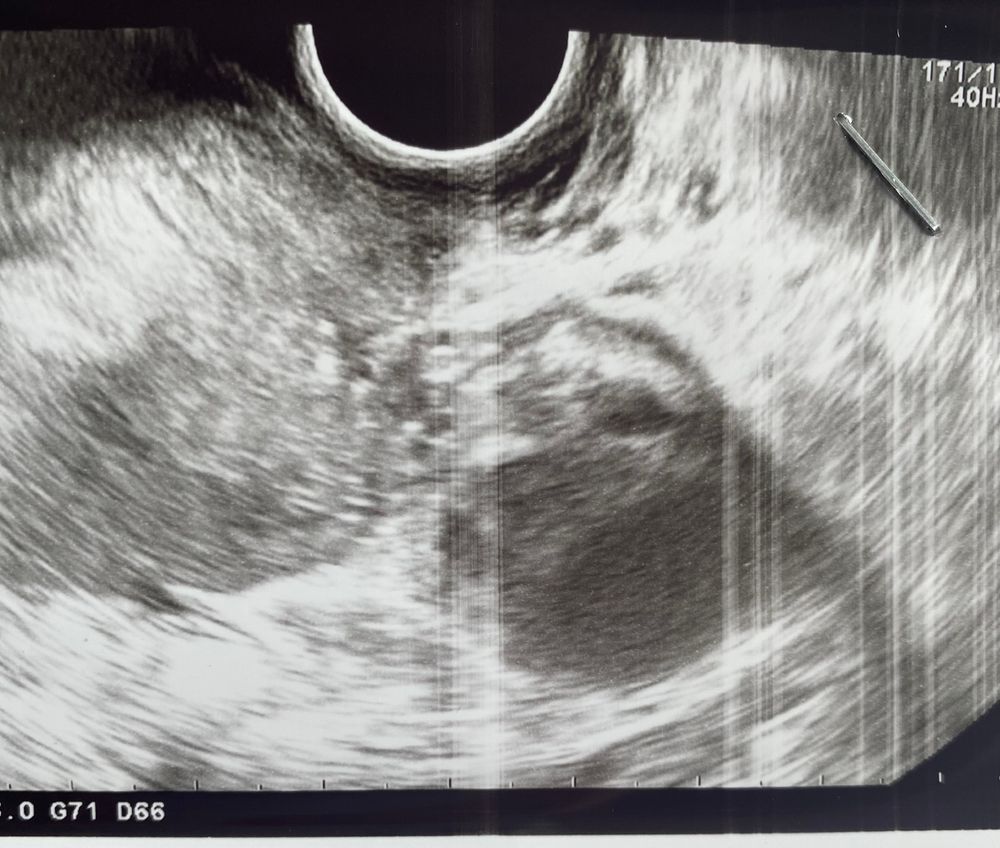

Не похоже ни на доминантный фолликул, ни на жт.

Дарья, он просто очень странно выглядит - вроде и лопнул, а вроде и нет, и внутри ещё эхогенные образования. Сложно сказать что это. А узистка разве не сказала?

Виктория, а эхогенное образование бывает в желтом теле? узист была не моя, моя в отпуске. За день до этого моя говорила, что фолликул 20 мм и эндометрий 10. А вот эта сказала, что после укола не лопнул и вообще он 18 мм. А эндометрий 6! Куда делся за полутора суток. Могу предположить, что сдулся. Моя мерила через день и в субботу он уже был 18! Поэтому ничего не понятно. Да и фолликул последний на фолликул не похож

Дарья, может он правда сдувается, поэтому так странно выглядит. А может только лопнул поэтому такой. Сложно сказать.

Такие вещи по фото не оцениваются) надо еще смотреть кровотоки ЦДК, есть ли взвесь , это все смотрится только в динамической картинке, а не на фото.